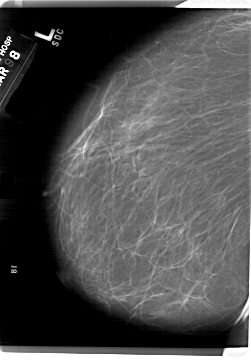

A_1815_1.LEFT_MLO

LEFT_CC LINES 6871 PIXELS_PER_LINE 5251 BITS_PER_PIXEL 12 RESOLUTION 43.5 NON_OVERLAY

LEFT_MLO LINES 6871 PIXELS_PER_LINE 4756 BITS_PER_PIXEL 12 RESOLUTION 43.5 NON_OVERLAY